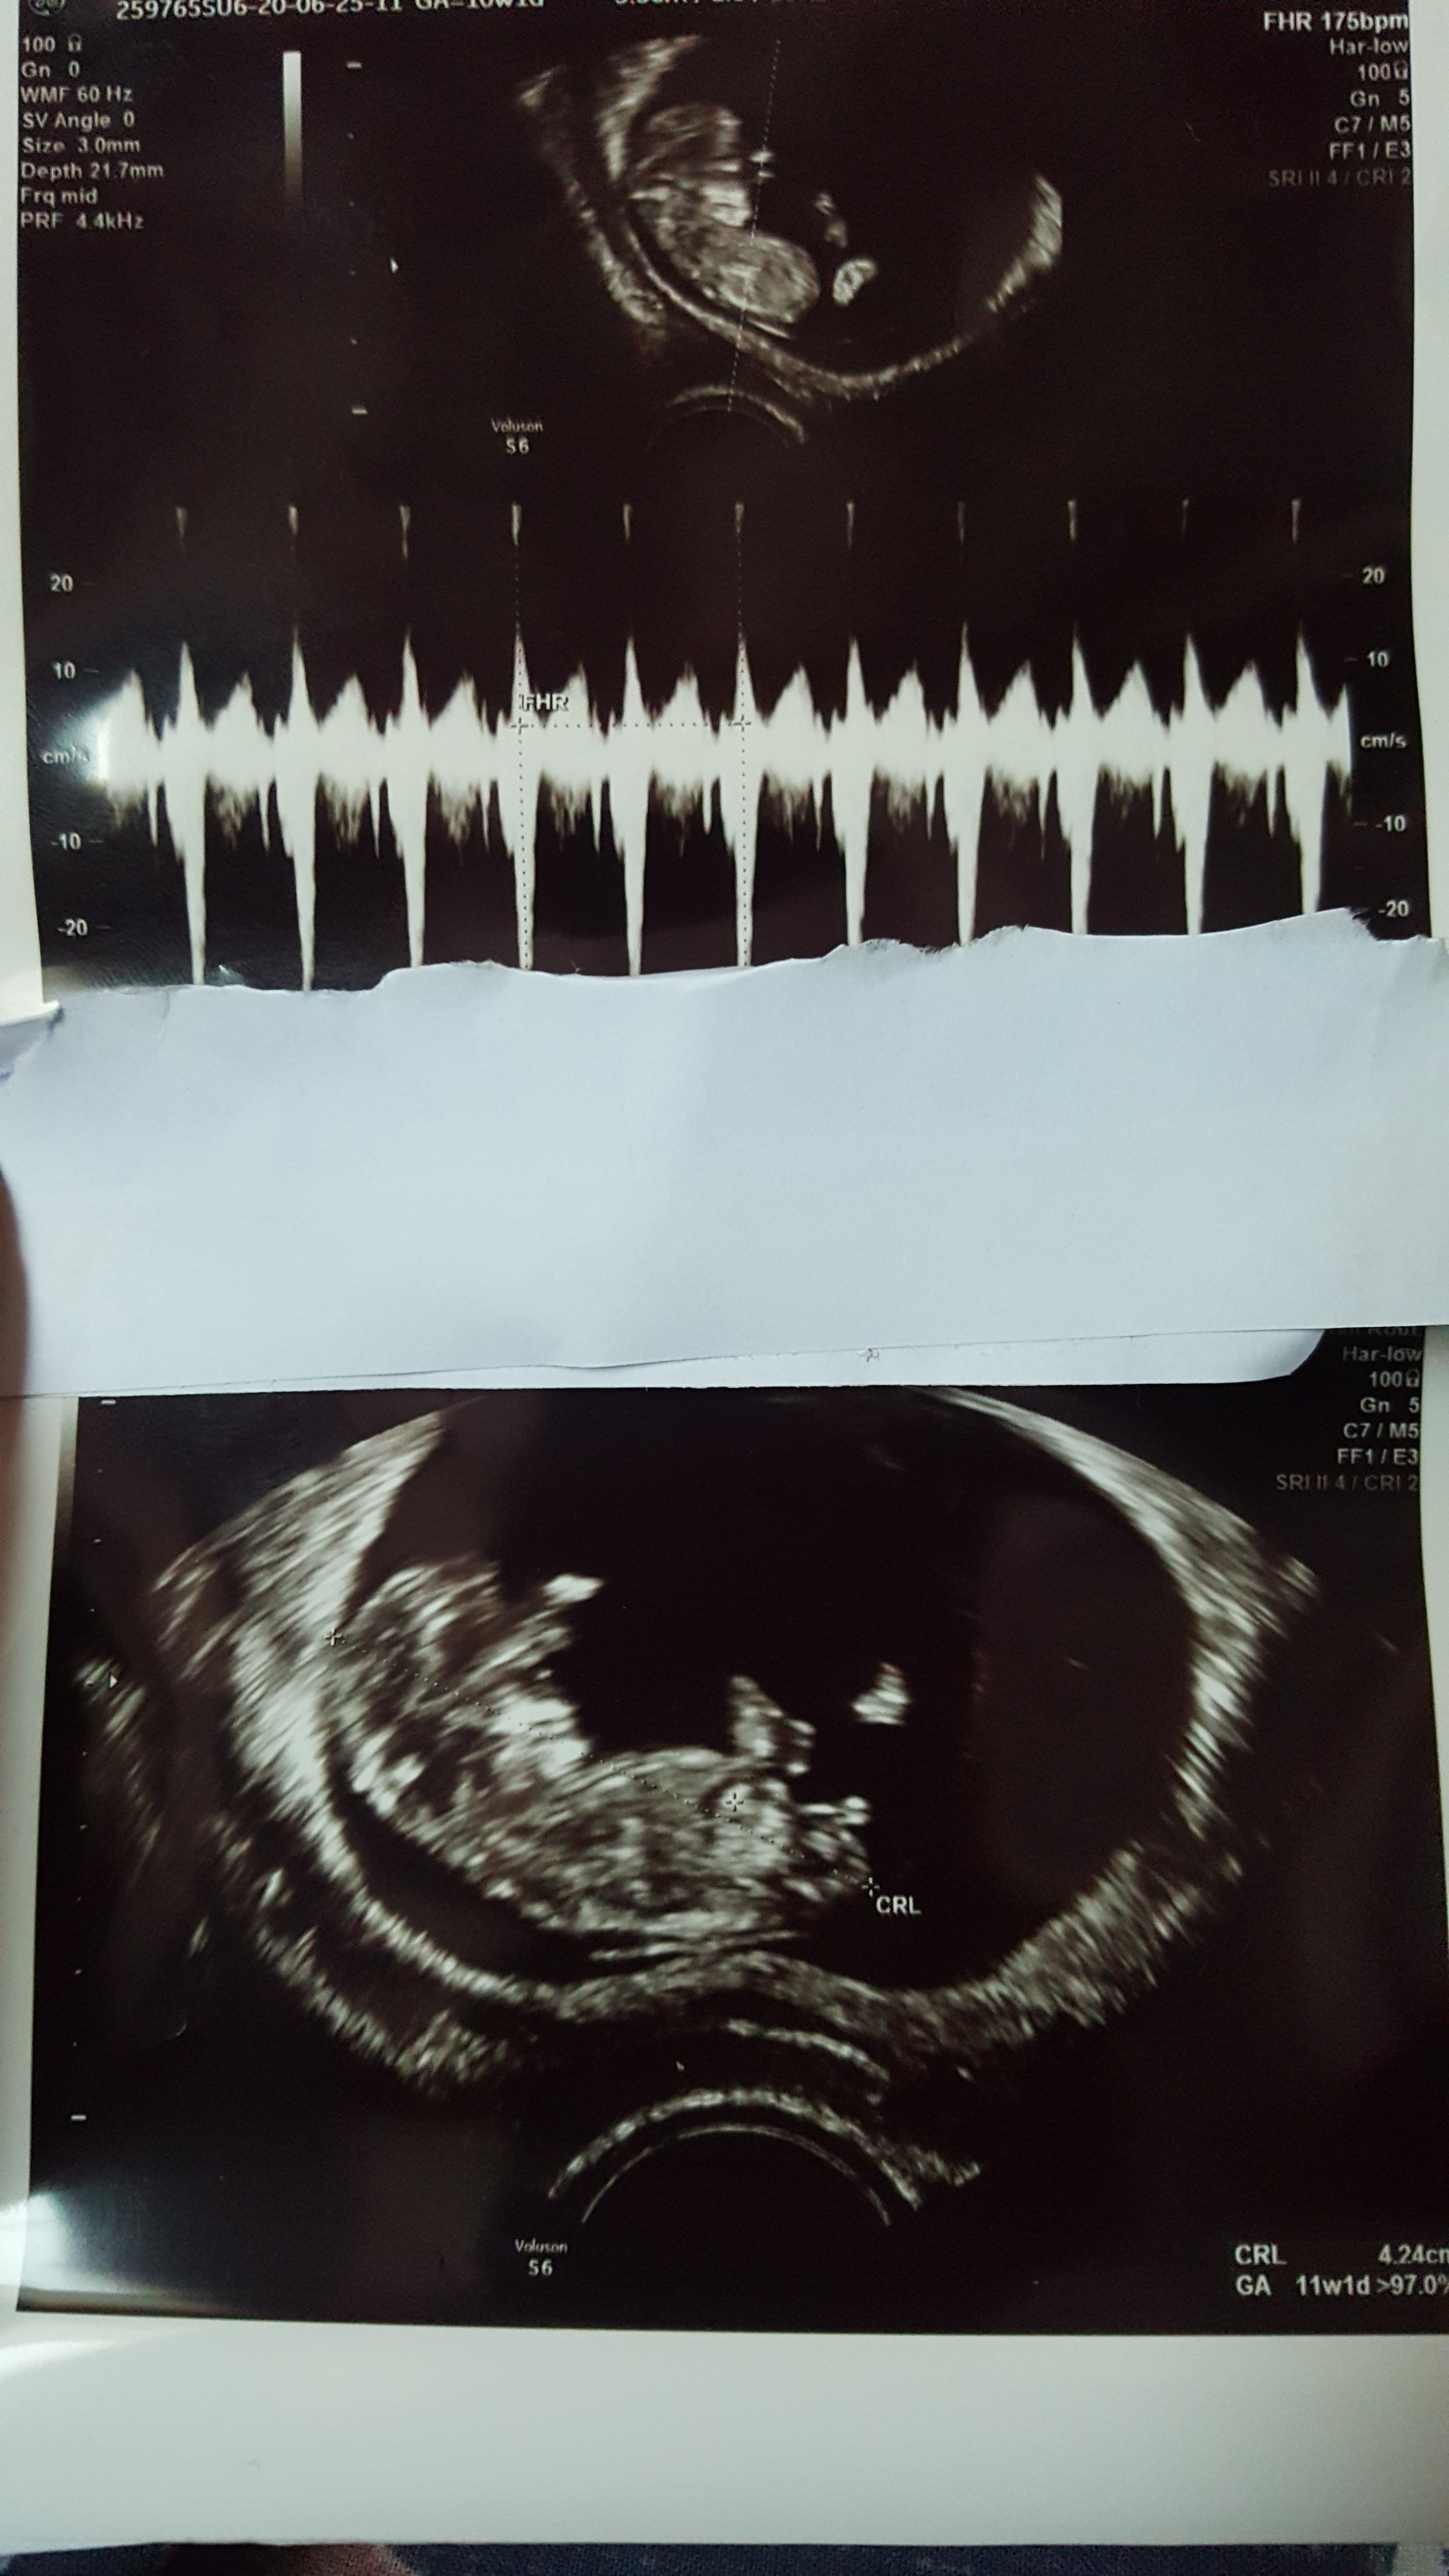

Moje badania prenatalne trwały chyba z 1,5 h....Masakra! Dzieciaczek ewidentnie nie chciał się ułożyć, żeby można było zmierzyć przyzierność karku, więc Pani doktor próbowała i usg brzuszne, potem dopochowo, potem znowu brzuszne, trzęsła mi tym podbrzuszem, żeby dzieciaczek się poruszył i zmienił pozycje, ale nic...W końcu zrezygnowała i mówi do mnie „musi Pani iść na pół godziny na spacer i najlepiej zjeść coś słodkiego”

Warto było, bo z usg wszystko wyszło dobrze, krew pobrana, ale wyniki dopiero za jakiś tydzień.

Ps. Na 80% dziewczynka, ale przeczuwałam to. Na razie partnerowi nie mówię, bo biedaczek już planuje, że będzie syna trenował w piłkę